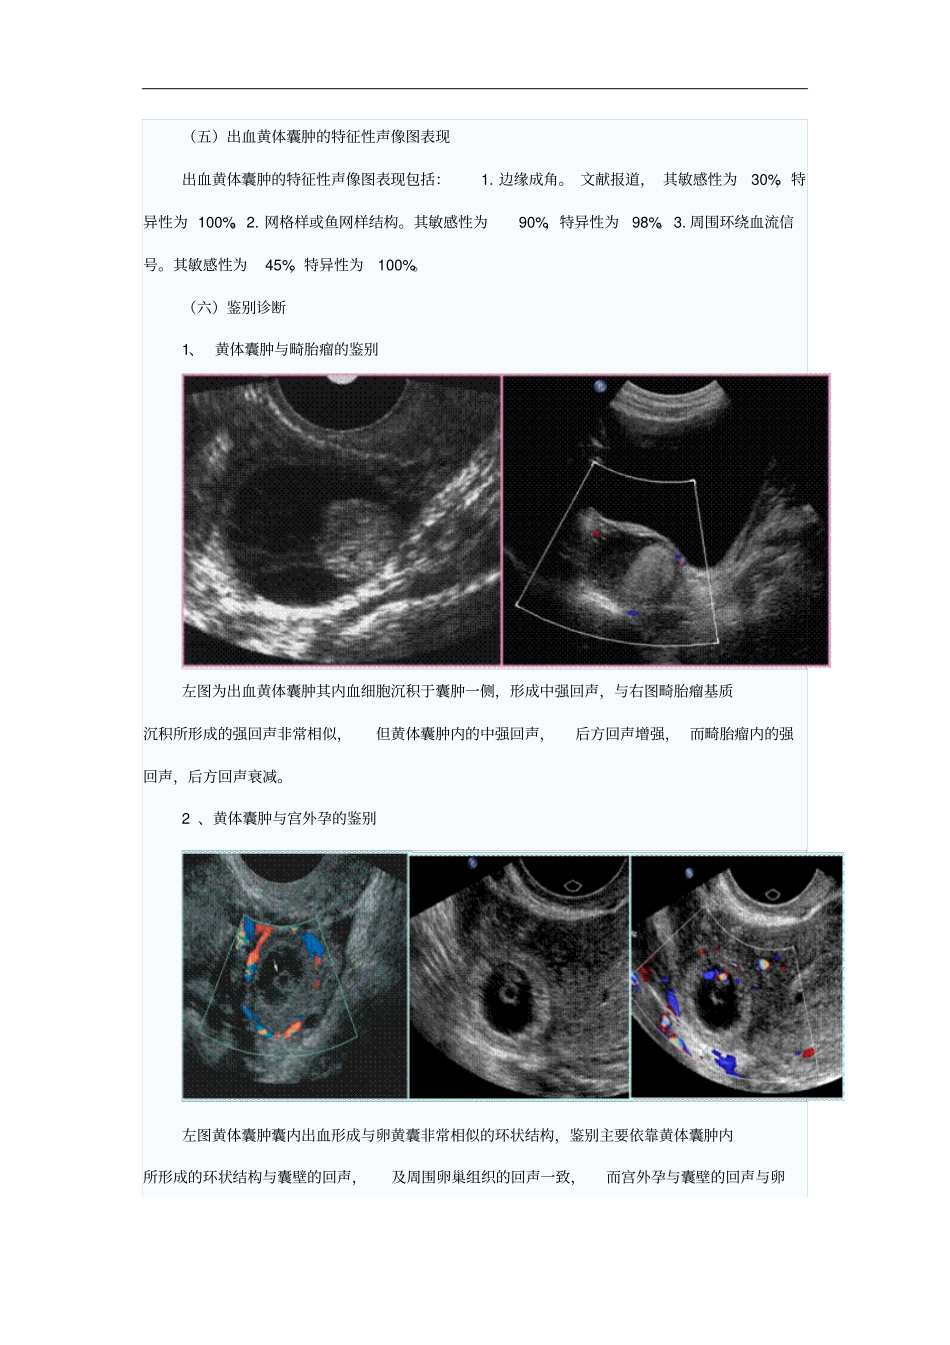

卵巢病变的超声诊断北京协和医院齐振红写在课前的话卵巢病变种类繁多,给临床的诊断及鉴别诊断增加了一定难度,临床上应用经腹超声和经阴道超声检查方法提高了卵巢病变诊断的符合率,为疾病的诊疗提供了有效的参考。一、卵巢病变的超声检查概述(一)卵巢病变的超声检查方法卵巢病变的超声检查方法,主要是经阴道超声和经腹超声。经阴道超声探头频率高且接近盆腔内结构, 有利于小病灶的检出及观察病变的边界、边缘、内部回声及内部血流信号。大的卵巢病变因阴道超声不能显示其全貌,最好使用经腹超声。(二)经阴道超声和经腹超声所显示的正常卵巢左图是使用经阴道超声检查方法所显示的正常卵巢及边界,内部的每一个卵泡均清晰显示, 因此经阴道超声对卵巢病变的敏感性很高,且有利于多囊卵巢的检出。右图是经腹超声所显示的正常卵巢,卵巢边界不如经阴道超声清晰,且仅能看到较大的卵泡,小卵泡显示不清。(三)卵巢病变的声像图特点卵巢组织学构成复杂,肿瘤分类繁多,声像图表现也多种多样,绝大多数病变超声常难以判断其病理类型,仅少部分病变有特征性声像图表现,超声可判断其病理类型,如成熟畸胎瘤、卵巢纤维瘤等。(四)卵巢病变的特点另外,卵巢黄体囊肿作为生理性病变,单纯囊肿超声容易诊断,囊肿合并出血时声像图表现多种多样,可与多种卵巢肿瘤声像图相似,超声易误诊。(五)超声在卵巢病变中的作用因此在卵巢病变的诊断中,超声需要解决两方面问题:1. 卵巢病变是生理性还是病理性?这一点非常重要。超声如能准确诊断出生理性病变,可使患者避免不必要的治疗,并减轻患者的精神压力。2. 卵巢病变良、恶性的判断。对于临床选择治疗方案有指导意义。二、卵巢黄体囊肿(一)卵巢黄体正常月经成熟卵泡排出卵子后,卵泡壁塌陷,血液流入腔内凝成血块形成血体,卵泡壁的破口很快被纤维蛋白封闭修复,血被吸收而形成黄体。(二)卵巢黄体囊肿在月经黄体或妊娠黄体基础上,由于卵泡刺激素( follicle stimulating hormone ,FSH) 和黄体生成素 (luteinizing hormone , LH) 平衡失调,致黄体功能活跃,腔隙大,内含较多液体而形成黄体囊肿。(三)出血黄体囊肿黄体囊肿壁上血管无肌层,因此容易出血形成出血黄体囊肿,卵巢黄体囊肿囊内出血会经历出血、血液与囊液混合、血细胞沉积、 血液凝固、 血块回缩及血清释放等病理生理阶段,但各阶段亦可同时出现于一个病灶内。(四)卵巢出血黄体囊肿因此,卵巢出血黄体囊肿可有...